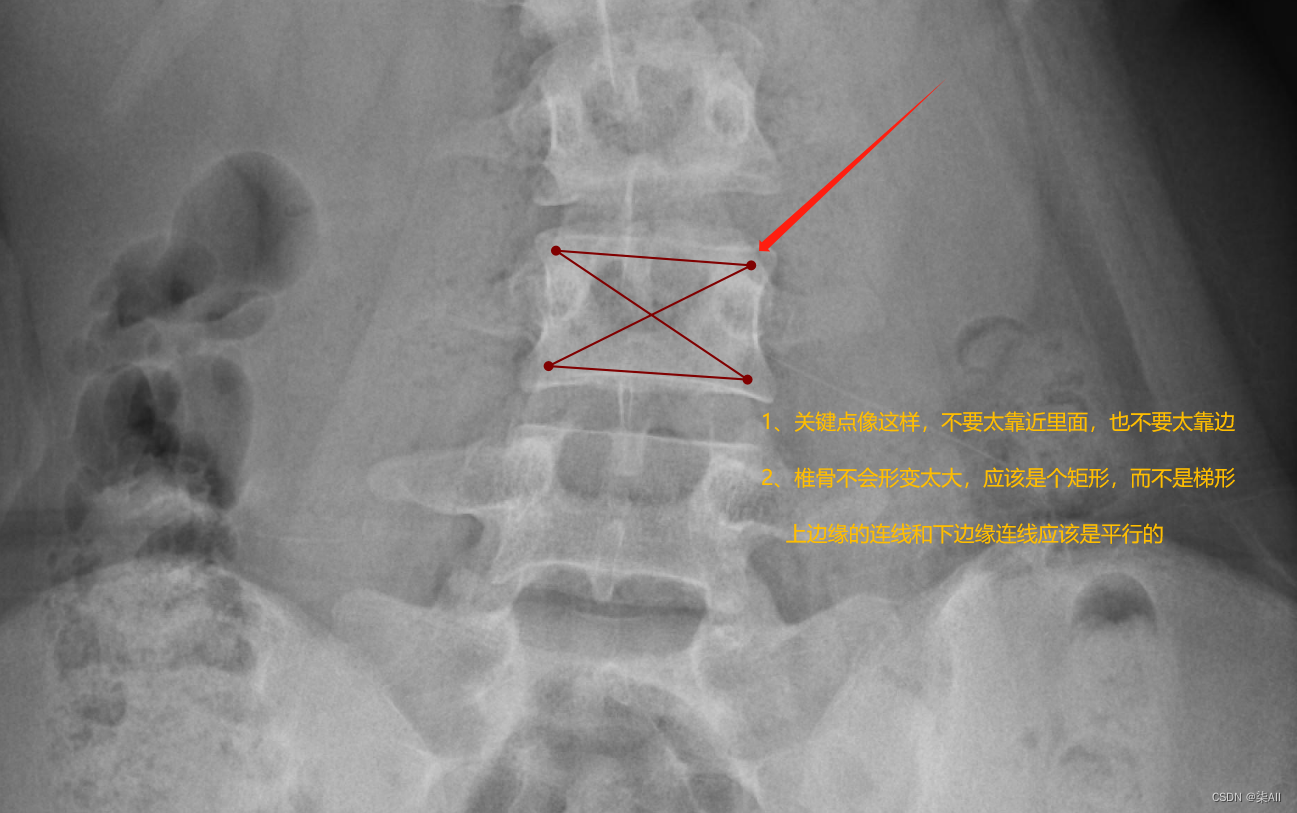

- (1)标注的椎体应该近似是一个矩形,而不是梯形 如下图

(1)标注的椎体应该近似是一个矩形,而不是梯形 如下图